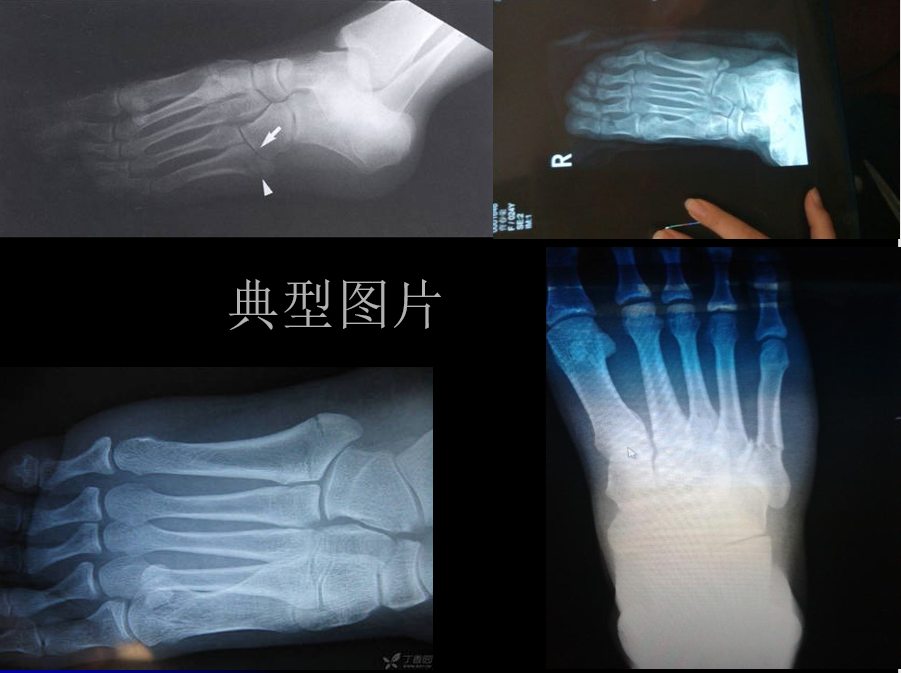

第五跖骨Ⅰ区骨折分型:Ekrol等把第五跖骨Ⅰ区骨折按部位从近而远又分为3个类型:(如图所示)

• 1型:是粗隆尖部骨折;

• 2型:是从第五跖骨基底到第五跖骨-骰骨关节面的斜形骨折;

• 3型:是通到第四跖骨关节面的横行骨折。

过去,1区、2区骨折可以采取保守治疗,3区有症状的应力性骨折、骨不连应积极手术治疗。

目前,非移位的1区、2区骨折保守治疗效果良好,对于移位的1区、2区骨折(涉及关节面或有台阶出现),手术治疗要优于保守治疗。虽然还存在争议,但大多认为,对于要求较高的患者(如运动员)即使无明显移位也提倡手术治疗。